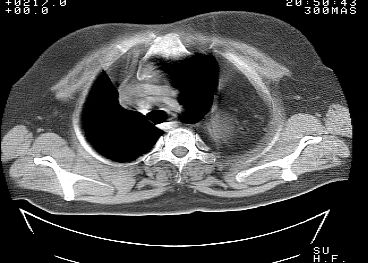

标题: CT10753:女, 64岁 隔疝 [打印本页]

标题: CT10753:女, 64岁 隔疝

女, 64岁 三十年前胸部外伤史, 间断胸闷,

典型左侧膈疝,疝出物为胃和大网膜,纵隔右移

同意左侧膈疝,不过,有过外伤史,左肺有受压征象,同时有胸膜增厚。

左侧隔疝(创伤性?),与外伤关系大。